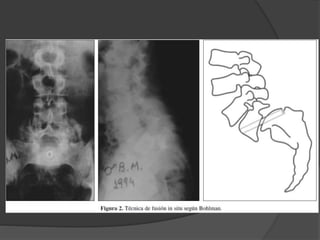

 Espondilolistesis deAlto Grado - Artrodesis in situ - Descompresión y artrodesis posterior - Reducción artrodesis 360 - Resección de L5 y APL L4 – S1

 Espondilolistesis de Alto Grado

- Artrodesis in situ

- Descompresión y artrodesis posterior

- Reducción artrodesis 360

- Resección de L5 y APL L4 – S1